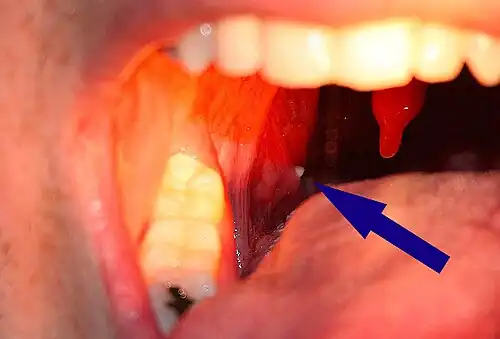

A tonsillolith lodged in the tonsillar crypt | |

A tonsillolith protrudes from the tonsil

Large tonsillolith half exposed on tonsil

Closeup of a tonsillolith